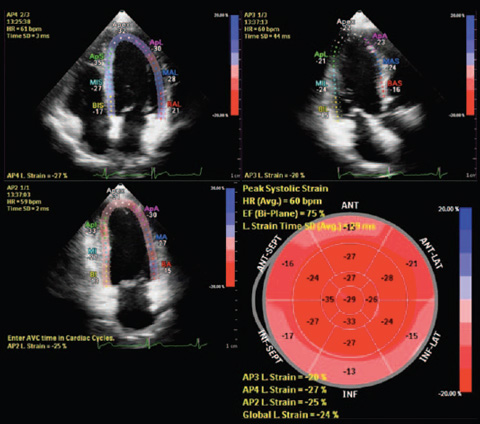

Nelle indagini a ultrasuoni Anatomical Intelligence esamina i dati ecografici di un paziente e applica l'intelligenza adattiva del sistema con modelli anatomici 3D per ottenere più facilmente risultati più riproducibili. Gli strumenti di Anatomical Intelligence, come HeartModel, utilizzano funzionalità avanzate di modellazione degli organi, sezionamento delle immagini e quantificazione convalidata per agevolare l'esecuzione degli esami ecografici e favorirne la riproducibilità offrendo al contempo nuovi livelli di informazioni cliniche, per rispondere alle difficoltà economiche e cliniche con cui si confrontano gli ambienti sanitari odierni.

Gli strumenti di Anatomical Intelligence convertono le immagini in risposte

Applicazioni della tecnologia Anatomical Intelligence